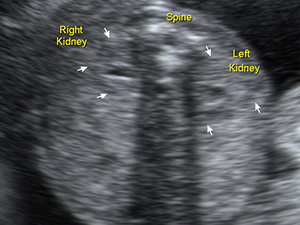

Abdomen